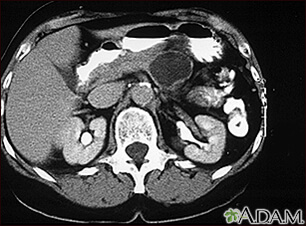

Поширені аномалії, що виявляються на КТ

За допомогою КТ можна виявити цілий ряд патологій, включаючи пухлини, кісти та інші утворення. КТ-сканування також корисне для виявлення переломів кісток, захворювань легенів і згустків крові.

Однією з найпоширеніших патологій, що виявляються на КТ, є вузлики в легенях. Ці невеликі утворення можуть бути доброякісними або раковими, і для визначення їхньої природи може знадобитися подальше обстеження.